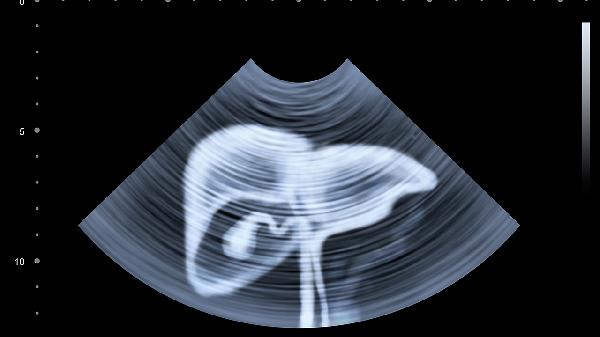

7、肝癌:丙肝是肝癌的重要危险因素,患者应定期进行肝脏超声和甲胎蛋白检查,早期发现肝癌。治疗包括手术切除、射频消融、靶向治疗等。